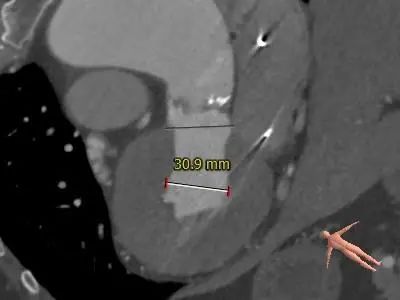

主动脉根部测量

3.推荐22mm球囊预扩,根据球扩后腰征决定AV26还是AV29瓣膜,瓣环下2mm定位释放,建议释放后调整至右前斜足位 RAO 6 CRA 35 左右进一步确定人工瓣膜展开形态。